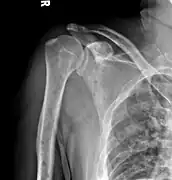

The diagnostic examination of a person with suspected multiple myeloma typically includes a skeletal survey. This is a series of X-rays of the skull, axial skeleton, and proximal long bones. Myeloma activity sometimes appears as "lytic lesions" (with local disappearance of normal bone due to resorption). And on the skull X-ray as "punched-out lesions" (pepper-pot skull). Lesions may also be sclerotic, which is seen as radiodense.[48] Overall, the radiodensity of myeloma is between −30 and 120 Hounsfield units (HU).[49] Magnetic resonance imaging is more sensitive than simple X-rays in the detection of lytic lesions, and may supersede a skeletal survey, especially when vertebral disease is suspected. Occasionally, a CT scan is performed to measure the size of soft-tissue plasmacytomas. Bone scans are typically not of any additional value in the workup of people with myeloma (no new bone formation; lytic lesions not well visualized on bone scan).

-

Multiple myeloma in the upper arm -

Humerus with multiple myeloma lesions -

Same humerus before, with just subtle lesions